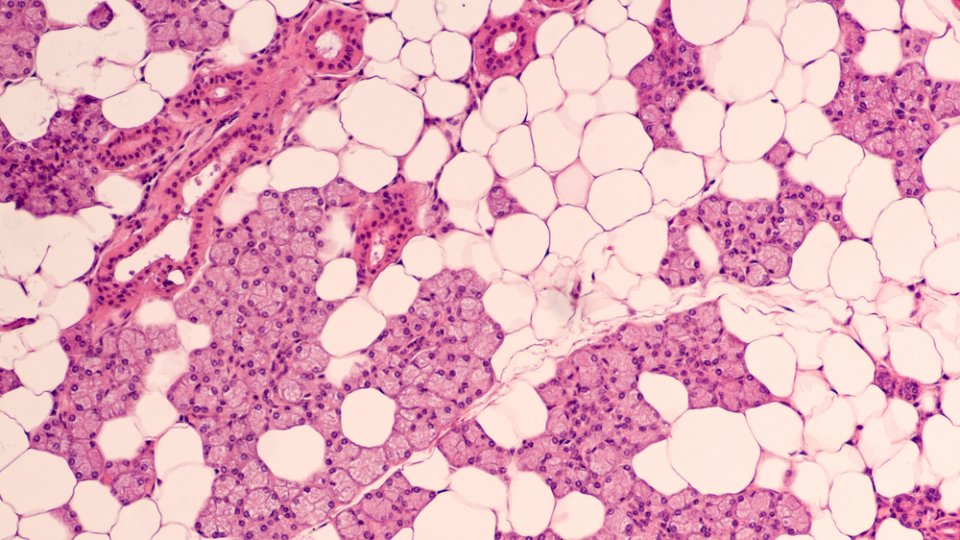

İyi Huylu Tümörler: Kanserli olmayan tümörlerdir. Genellikle parotis bezinde (kulak önü) bulunur. Yaygın görülen iyi huylu parotis tümörü genellikle çenenin arkası veya kulak memesinin hemen altında ağrısız, yavaş büyüyen bir yumrudur.

Kötü Huylu Tümörler: Kanserli tümörlerdir ve genellikle nadir görülür. Ancak saldırganlık açısından farklılık gösterebilir. Radyasyon maruziyeti ve sjogren sendromu tükürük bezleri için bilinen risk faktörleridir.